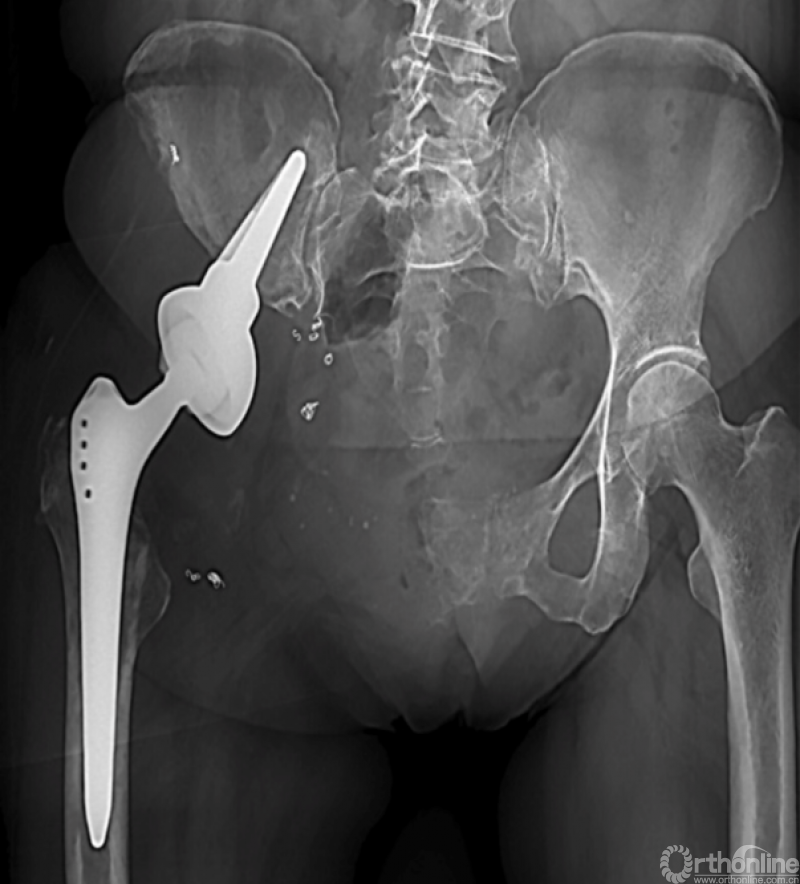

马鞍式假体未与宿主骨形成稳定的骨性连接,整体功能较差,并且并发症发生率较高[2-5](图1)。冰激凌假体与宿主骨的连接更加紧密,但不适合骨盆I区大部分切除的骨缺损,不能重建完整骨盆环[6-10](图2)。组配式半骨盆假体组装灵活,且可进行骨盆环完整重建,但其安装技术要求高,假体组件间存在断裂风险,不匹配得假体与宿主骨锚定将直接影响骨整合,最终易导致松动[1,11-15](图3)。

图1 马鞍式假体